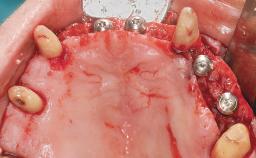

A 63-year-old male patient was referred for a consultation and treatment of partial edentulism in the maxilla. The patient presented with residual anterior teeth and declined a partial removable prosthesis. He reported that the maxillary posterior teeth had been extracted due to mobility and periodontal disease two months before the consultation. The patient’s chief complaint was that his residual maxillary teeth were mobile and that he was unable to chew. The patient’s desire was a stable and comfortable fixed maxillary rehabilitation. The patient was a light smoker (fewer than 10 cigarettes/ day), and his medical history was without significant findings. He was not on any regular medication at the time of consultation. The extraoral examination revealed a normal physiognomy with a correct distribution of the facial thirds. The patient presented a low lip line, and the transition line between teeth and soft tissues was not exposed during a forced smile.

# of Implants 6

Bone Augmentation Horizontal|Simultaneous

Defining Characteristics Fully edentulous upper jaw to be rehabilitated with four or more implants

Modality 6+ implants with immediate loading